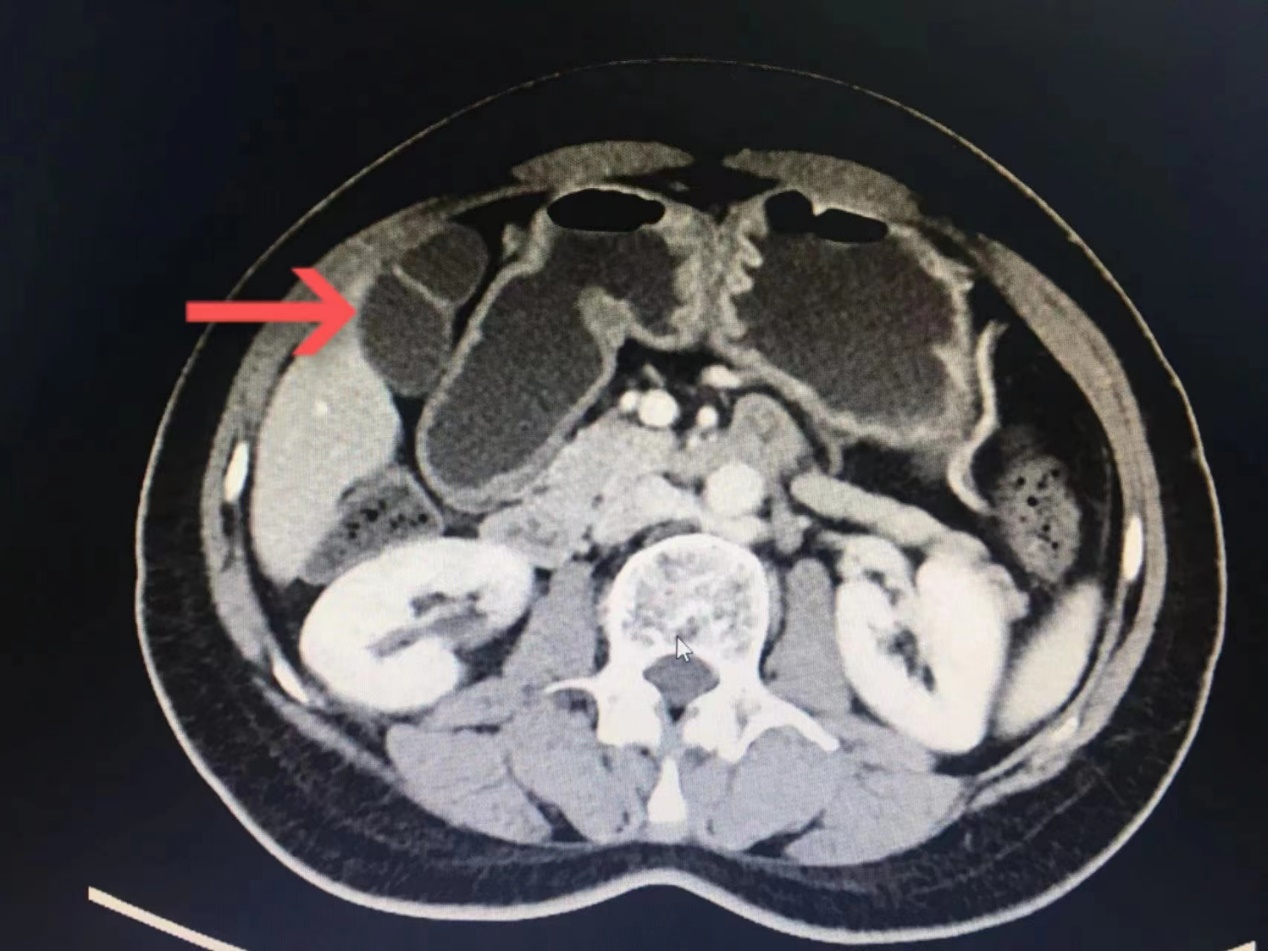

图2-葫芦状胆囊.png

图2  箭头标志处为葫芦状胆囊